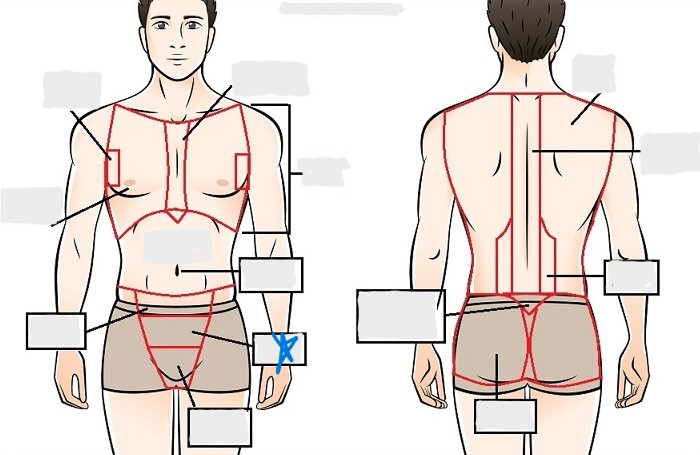

axial

cephalic

occipital

frontal

otic

orbital

nasal

oral

mental

cervical

dorsal

scapular

vertebral

lumbar

sacral

gluteal

thoracic

sternal

mammary

axillary

abdominal

umbilical

pelvic

inguinal

pubic

perineal

appendicular

acromial

brachial

antecubital

olecranal

antebrachial

carpal

manus

coxal

femoral

patellar

popliteal

crural

sural

peroneal

calcaneal

plantar